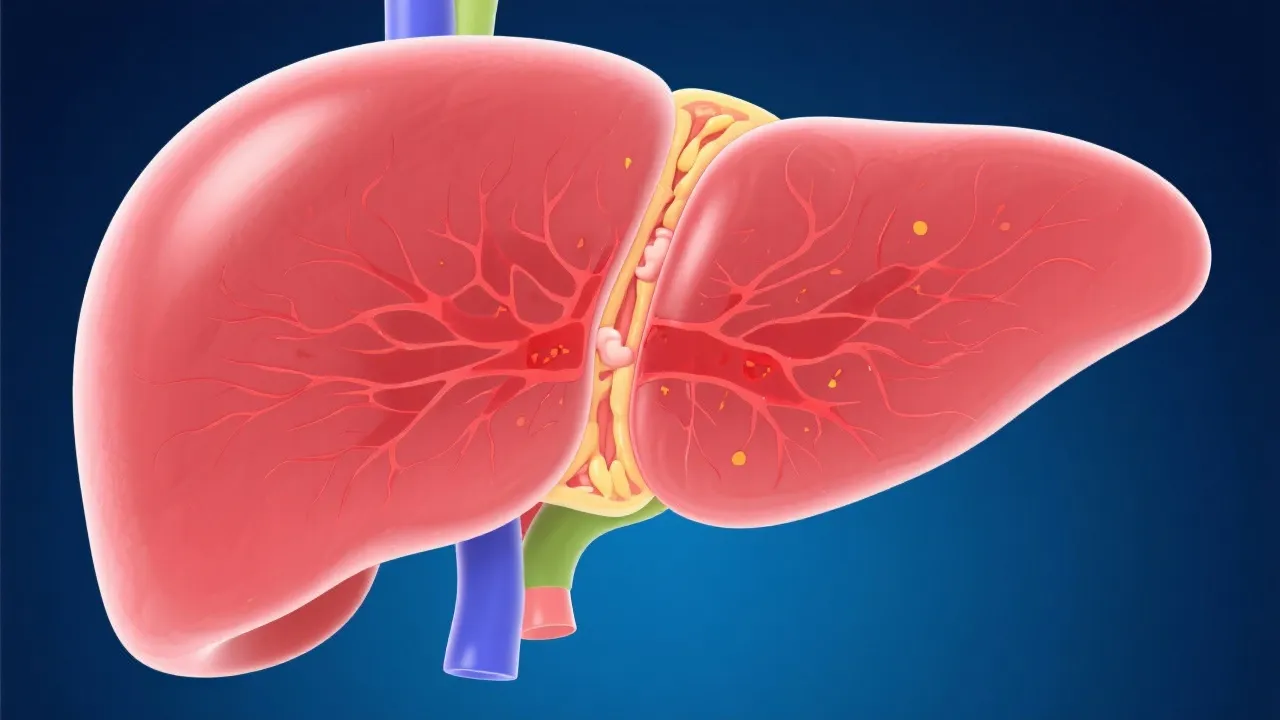

NASH develops as a result of fat accumulation in liver cells, leading to cell damage, inflammation, and, potentially, fibrosis. The liver, being a central metabolic organ, plays a pivotal role in lipid metabolism, and its dysregulation can prompt steatosis. This condition is often asymptomatic in its early stages, complicating timely diagnosis. The pathophysiology involves complex interactions between genetic predispositions, diet, and environmental factors, which together result in insulin resistance and oxidative stress. Genetic factors include polymorphisms in genes associated with lipid metabolism, such as the PNPLA3 gene, which has been identified as a major risk factor for NASH. These elements underscore the importance of understanding individual patient profiles for effective management strategies. Emerging studies are also focusing on gut microbiota's role in modulating liver inflammation and fat accumulation, suggesting a potential target for therapeutic interventions.

Diagnosing NASH necessitates a comprehensive approach due to its silent progression. Evaluations often involve liver function tests (LFTs), imaging modalities like ultrasound and MRI, and, in some cases, liver biopsy for exact staging. Liver function tests help assess the extent of liver dysfunction, although they can be normal even in significant liver disease. Non-invasive imaging, such as elastography, has gained attention for its ability to evaluate liver stiffness, which correlates with fibrosis. Innovations in non-invasive diagnostic tools are promising for assessing liver fibrosis degree without invasive procedures, enhancing patient comfort and compliance. These advancements, including serum biomarker panels and proprietary algorithms, are critical for early-stage identification, which is crucial in preventing the disease's progression to cirrhosis. As research evolves, the hope is to find a reliable test that can effectively differentiate between simple steatosis and NASH, particularly in individuals with risk factors but no overt symptoms.